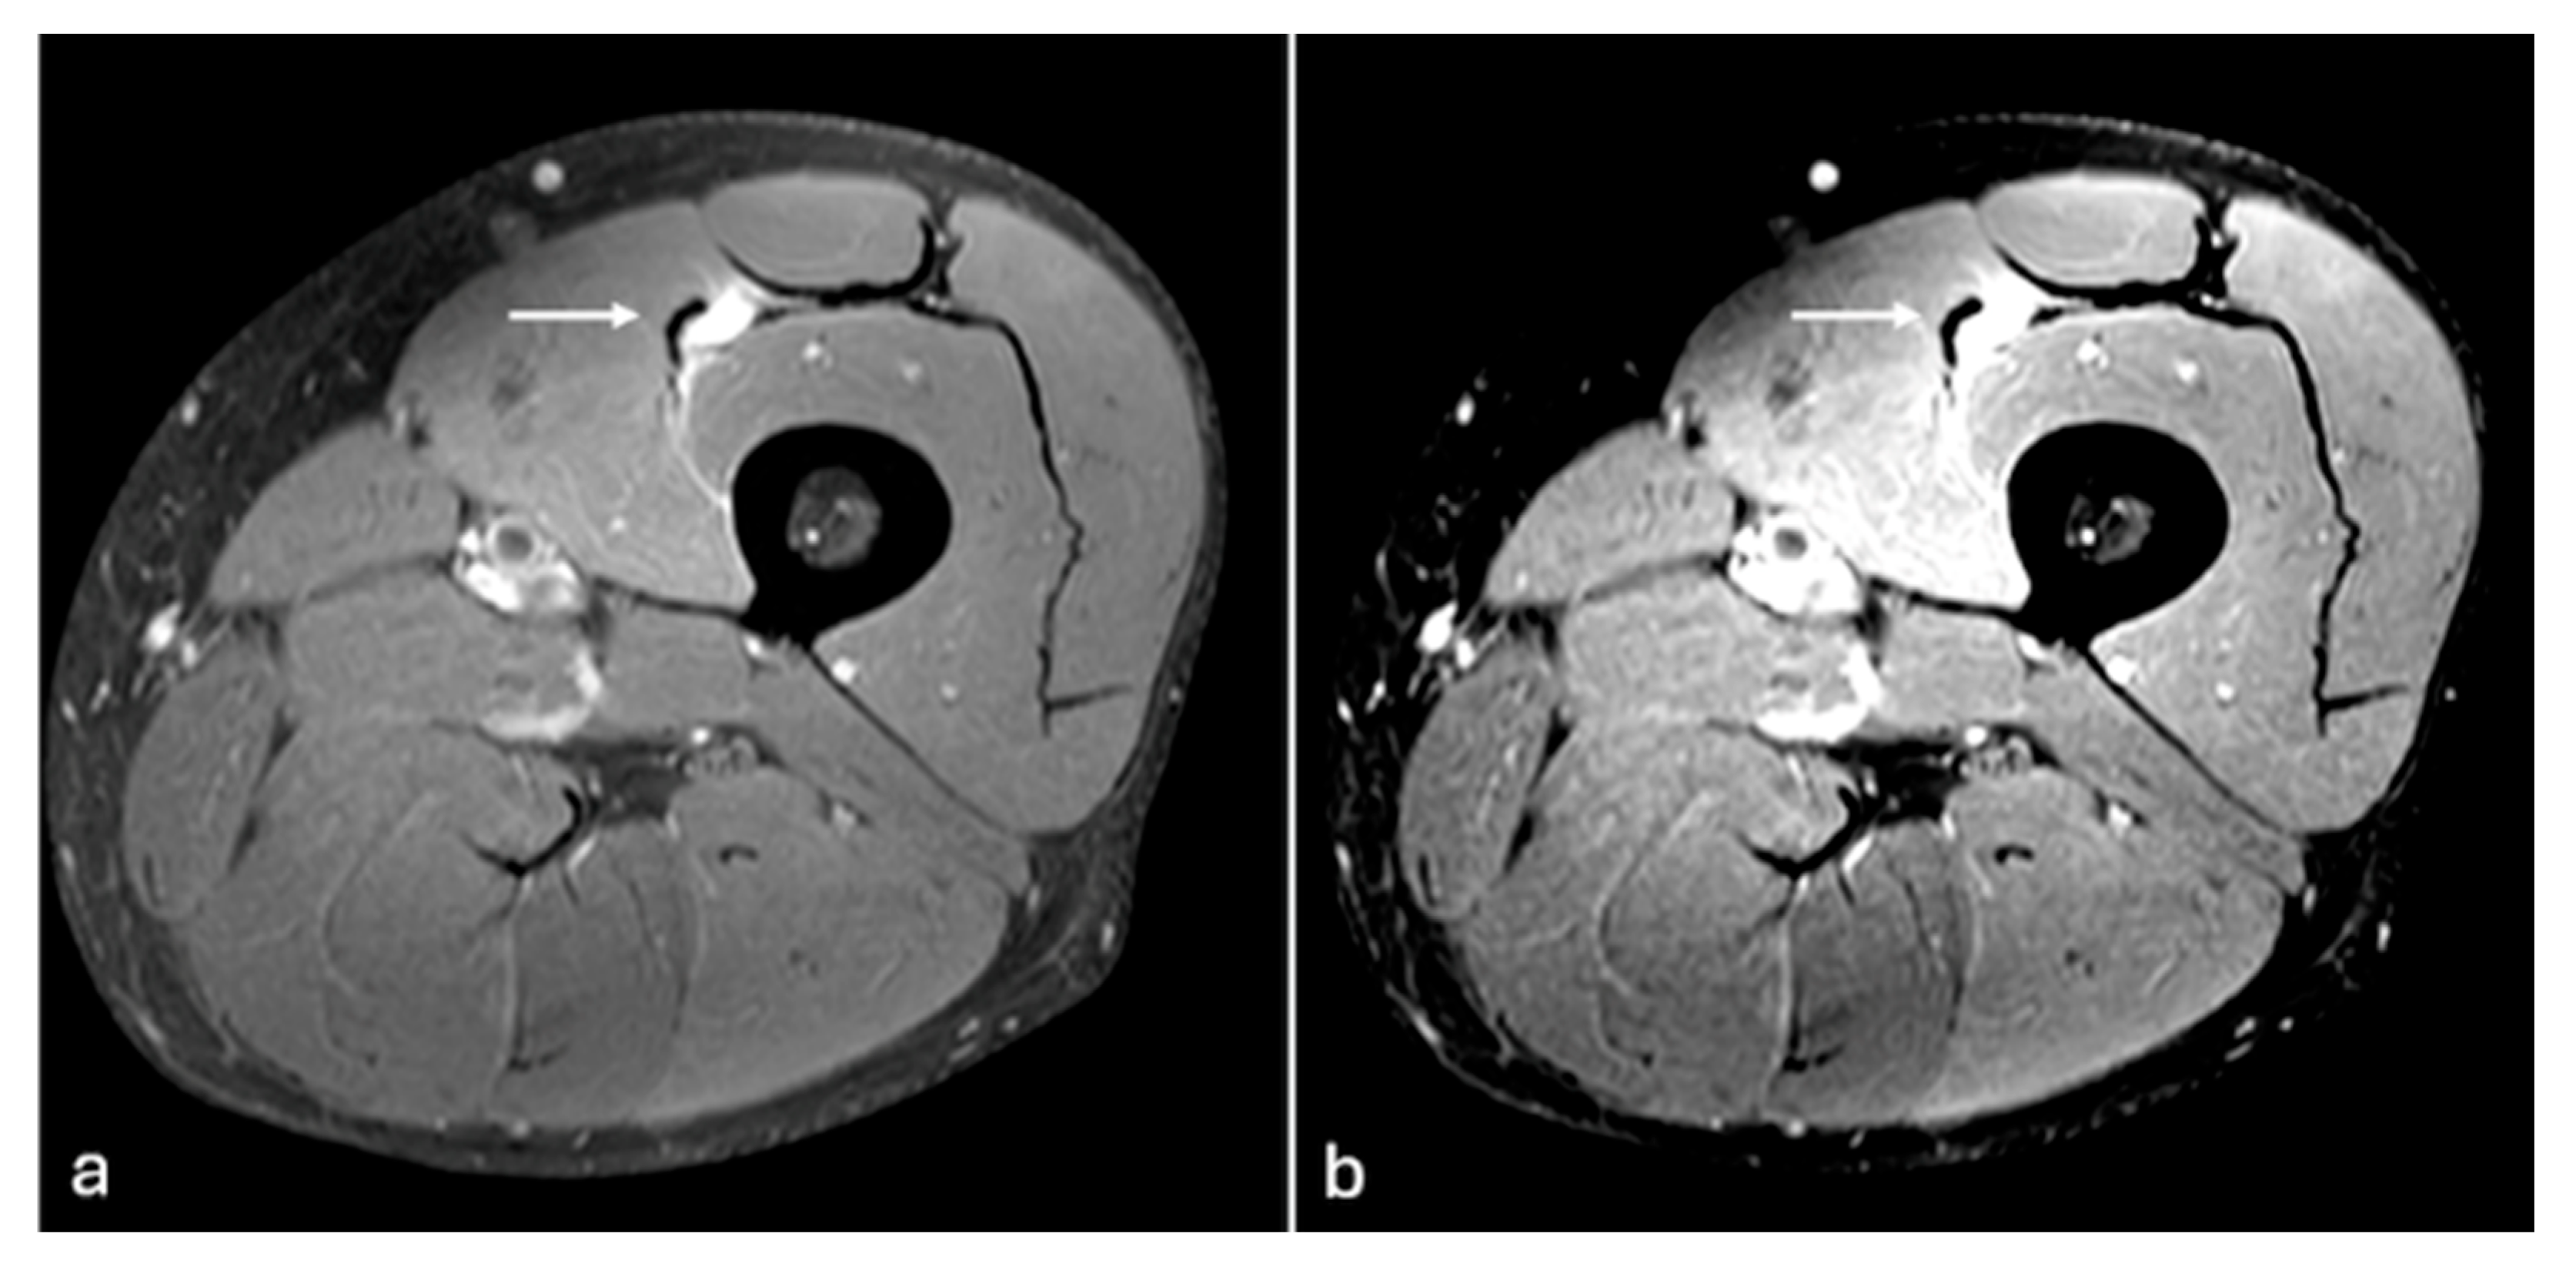

Figure 3. PDFS axial MR images of left leg (a,b). Changes in muscle oedema in tear of tibialis anterior (arrow) are better detected on the image with modified windowing (b) when compared to default windowing (a). W/L of the image (a)—1516/872, (b)—831/836.